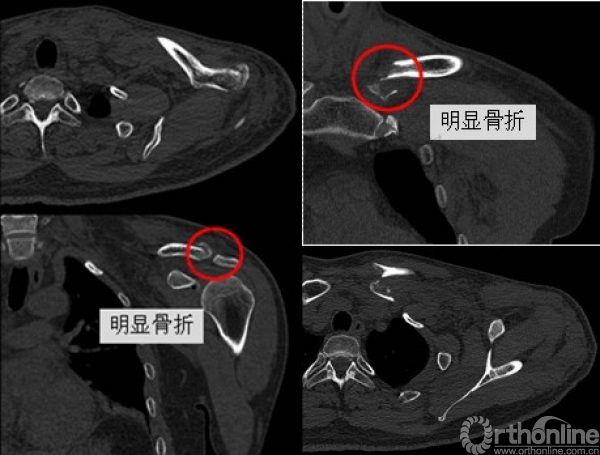

影像学检查—CT平扫

影像学检查—CT三维重建

1.创伤性漂浮锁骨(左侧)

(1)锁骨远端骨折

(2)锁骨近端骨折

(3)胸锁关节脱位

(一)仔细检查:避免遗漏一侧损伤或合并伤 X-ray + CT ……

(三)术后随诊:建议同时完善CT检查评估近端锁骨/胸锁关节情况